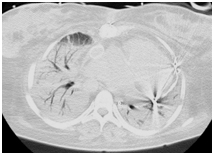

Figure 1 Tomographic aspect demonstrating Fontan pervium extracardiac tube.